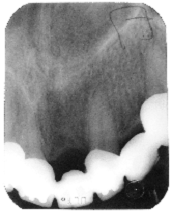

Fig. 11

Aspect radiologic de pe maxilarul inferior

cu o RPF. Se observa o ancorare meziala pe un rest monoradicular.

Observatii: erodarea insertiei intre DCR si restul radicular.

Cauzele posibile

Subevaluarea de catre medic a conditiei biomecanice a restului radicular;

Subdimensionarea DCR;

Conceperea si executarea unei RPF

supradimensionate.